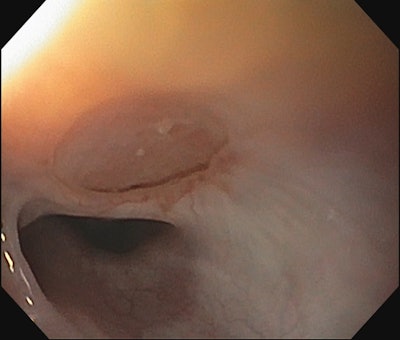

A TEF may be congenital or acquired. Most commonly, congenital TEF is associated with esophageal atresia (EA). The location and size of a fistula can help determine the best approach. Fistulas in the distal third of the trachea are usually best served by general surgery. Fistulas in the proximal third of the airway are often best addressed by otolaryngology and the middle third may be addressed by either discipline. H-type tracheoesophageal fistulas in the proximal third of the airway can be approached with a trans-tracheal approach to avoid lateral dissection and risk to the recurrent laryngeal nerve. This technique allows for multi-layer closure by working through a tracheotomy and separating the trachealis and esophagus around the periphery of the defect. The esophageal layer is then closed (Figure 1) followed by the placement of an interposition fascia graft and finally closure of the trachealis and tracheotomy.

Figure 1. Exposure of esophageal mucosa through an anterior tracheotomy overlying the TEF.